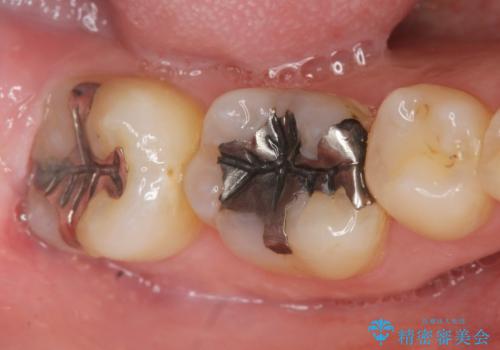

- 笑った時に見える銀歯を白くしたいと希望され来院されました。

現在入っている銀歯を丁寧に除去し、適合の良い精密なセラミックインレーによる修復を行います。